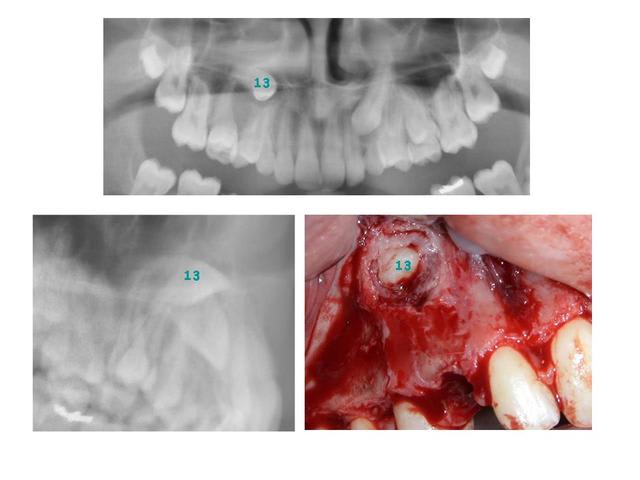

Suite et fin de la première série, voici le coupable :

La 14 n'était effectivement pas loin et j'ai dû reculer un peu son apex pour permettre à la 13 de descendre.

J’avais comme toi un doute avant d’aller la chercher et je me demandais si je n’allais pas avoir quelques difficultés à cause des incisives. En fait, j'ai dégagé relativement facilement sa couronne devant la 32. Elle est donc bien vestibulaire sans contestation possible.

Voici une photo per-op où on voit parfaitement sa situation. C’est la première photo faite, j’avais d’abord fixé une ligature, puis l’ai remplacée par un TMA pour pouvoir exercer un bras de levier vestibulaire.

Le téléprofil ici est trompeur, car on n’individualise pas bien les incisives.